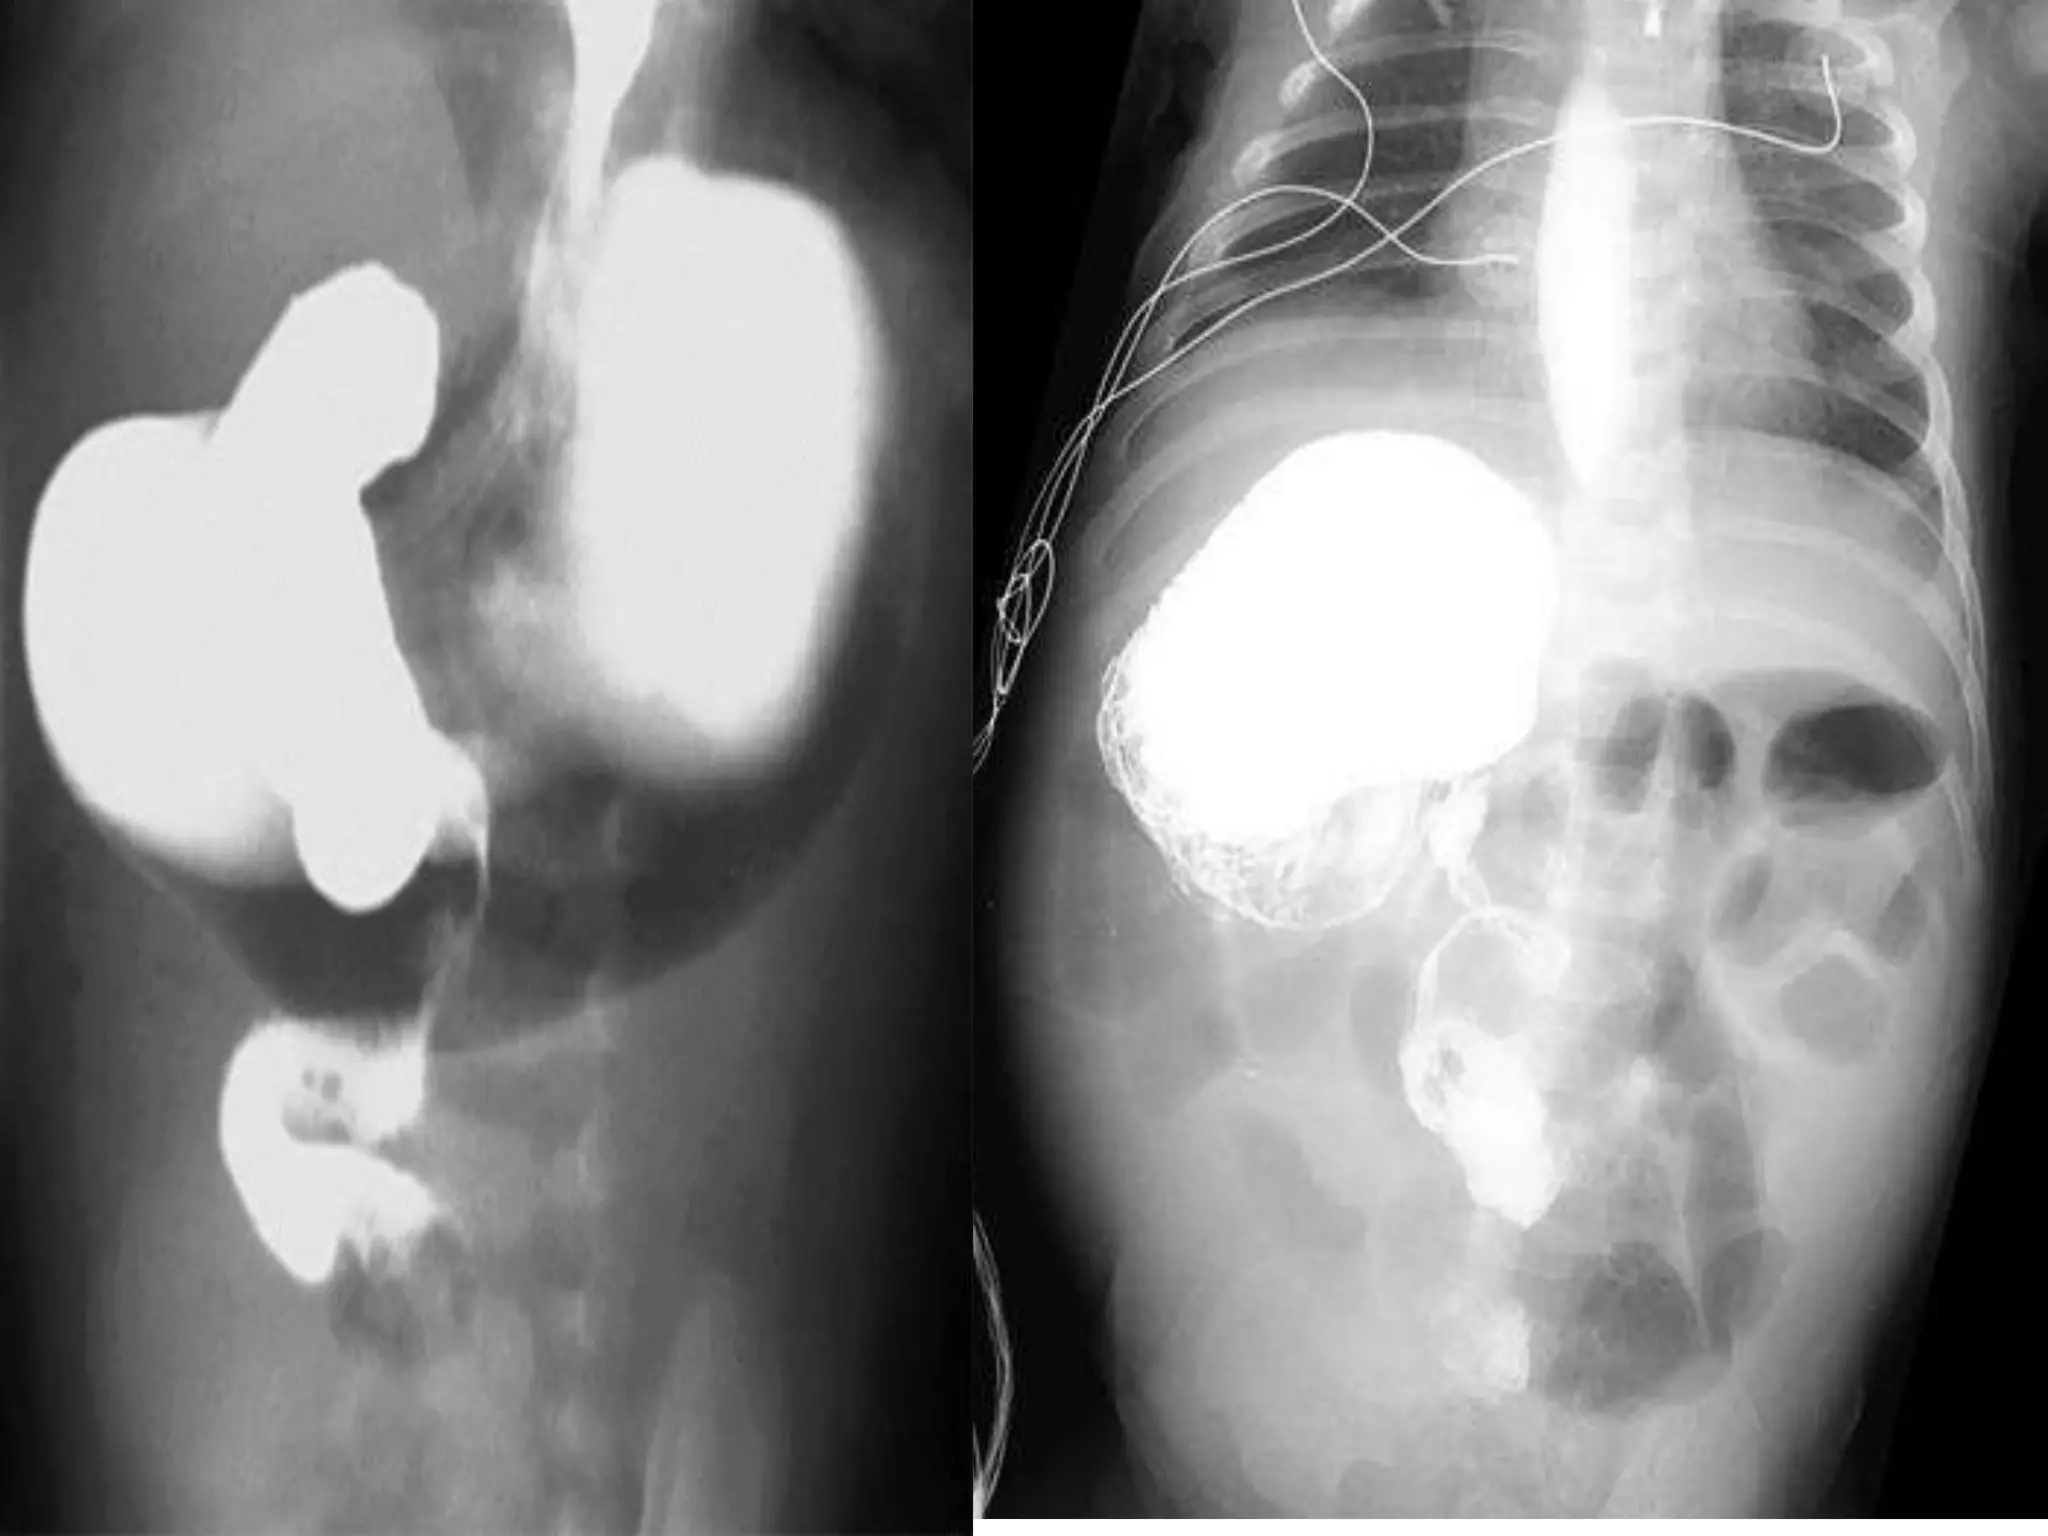

DIAGNOSIS

• Plain X-Ray.

• Doppler study.

• Upper contrast study.

• CT- scan.

DIAGNOSIS • Plain X-Ray. •Doppler study. • Upper contrast study. • CT- scan.